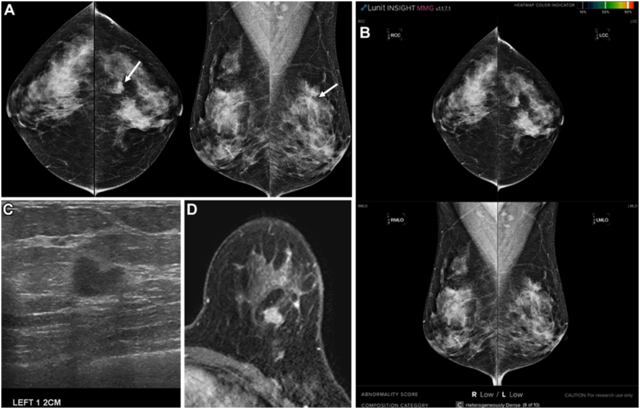

20일 의학계에 따르면 고려대학교 유방센터팀 (송성은 안암병원 영상의학과 교수, 우옥희 구로병원 교수) 연구팀은 ‘AI 스크리닝으로 놓친 침습성 유방암’이라는 제목의 논문을 영상의학 분야 최고 권위 학술지인 라디올로지(Radiology)에 최근 게재했다. 연구진은 2014년부터 2020년까지 진단된 1097건의 유방암을 대상으로 국내에서 개발된 상용 AI 소프트웨어(Lunit Insight MMG)를 이용해 유방촬영술 판독에서 침습성 유방암의 놓침률과 특성을 분석했다. 연구 결과 AI는 전체 유방암의 14%를 놓쳤으며, 분자 아형별로는 내강암 아형에서 17.2%, 삼중음성암 아형에서 14.5%, HER2 양성암 아형에서 놓침률이 9%로 나타났다

AI가 놓친 침습성 유방암의 주요 특징으로는 젊은 연령, 2cm 이하의 작은 종양, 낮은 조직학적 등급, 림프절 전이 적음, 낮은 Ki-67, 비유선구역(유방 외곽부) 위치, BI-RADS 4 범주의 영상 소견 등이 있었다. AI가 놓친 암의 61.7%는 영상의학과의사가 발견할 수 있는 암으로 평가되었으며, 놓친 원인으로는 치밀 유방, 비유선구역, 구조 왜곡, 미세석회화 등이 확인되었다.